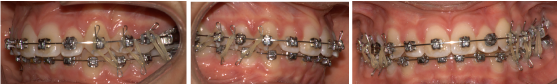

In 2015 brackets DAMON Q have been positioned in the upper arch, except on the tooth 2.2 and the tooth 2.3 has been exposed to put on it a botton (Figure 12)

Figure 12. BRACKET DAMON Q

Figure 16. INTRAORAL FINAL PHOTOS

Figure 17. EXTRAORAL FINAL PHOTOS